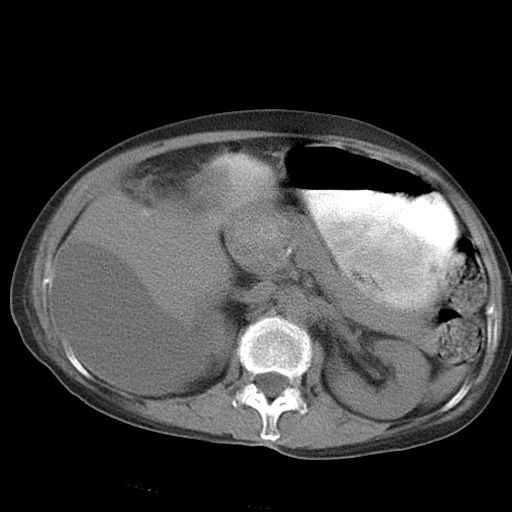

以下是引用dyqct在2006-12-7 21:08:00的发言:[br]考虑:1、肝内外胆管多发性结石伴肝左叶外侧段肝萎缩;[br] 2、右膈下多发脓肿;[br] 3、右侧少量胸腔积液、斜裂积液;[br] 4、左肾囊肿。

以下是引用jiazh在2006-12-7 20:37:00的发言:[br]肝脏周围半狐形低密度影,肝脏表面受压推移,考虑膈下脓肿可能性大;2、右侧胸腔积液

以下是引用拾荒者在2006-12-7 21:44:00的发言:[br]肝内外胆管多发结石,右膈下多发脓肿,右胸膜腔及叶间裂积液,左肾囊肿。[br] [br]